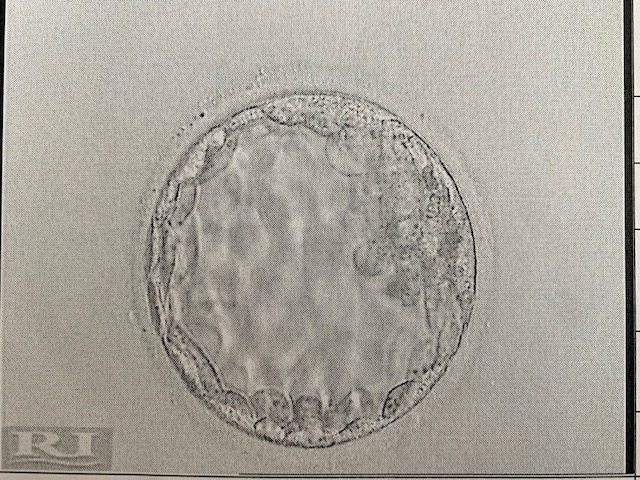

On 15th May 2019 we transferred two of our frozen embryos. A long time coming after Phil’s diagnosis last year, an emergency sperm freezing and then a fresh IVF cycle in February.

It was a big decision for us as we had only ever transferred one at a time before. We have always been fortunate that our blastocyst embryos have been good quality and we really did take the time to think about the implications of a multiple pregnancy and the possible risk of miscarriage. The general consensus from our clinic was that one was preferred but my age (38) allowed us the option for two.

On transfer day we were told that one embryo had thawed out beautifully but the other one was still catching up. The embryologist explained that the embryo was still above the margins that they are happy to transfer and there was a good chance once in my uterus it would catch up. But we were given the option to use another embryo (we had another 5) but we felt like after all the dilemma with transferring two, this was the universes way of making that decision for us and we transferred both understanding that one maybe wasn’t as viable as the other. Six weeks of injections and tablets and we were once again excited to have our embryos on board! IVF no.6.